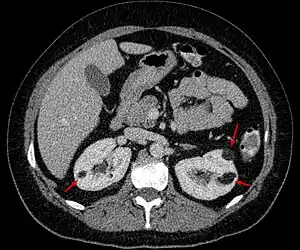

Angiomyolipoma in both kidneys (arrows) in computer tomography. The tumours are hypodense (dark) due to fat content.

Angiomyolipomas are strongly associated with the genetic disease tuberous sclerosis, in which most individuals have several angiomyolipomas affecting both kidneys. They are also commonly found in women with the rare lung disease lymphangioleiomyomatosis. Angiomyolipomas are less commonly found in the liver and rarely in other organs. Whether associated with these diseases or sporadic, angiomyolipomas are caused by mutations in either the TSC1 or TSC2 genes, which govern cell growth and proliferation. They are composed of blood vessels, smooth muscle cells, and fat cells.